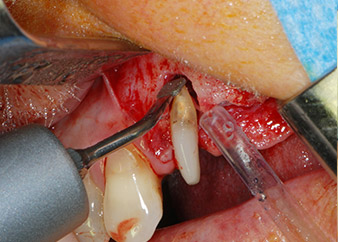

periodontium

Fig. 4: To preserve the tooth as a temporary abutment, the periodontium was debrided with piezoelectric equipment …

However, we maintained our initial plan to retain both teeth as temporary bridge abutments during the six-months osseointegration period of the implants. At reentry, the situation would have to be reassessed. First, in an attempt to manage the endo-perio problem, the remaining root surface was carefully debrided with piezoelectric equipment (Piezomed, W&H, used with the spatula-shaped insert S1, originally designed for erosion of the lateral sinus wall) (Fig. 4).